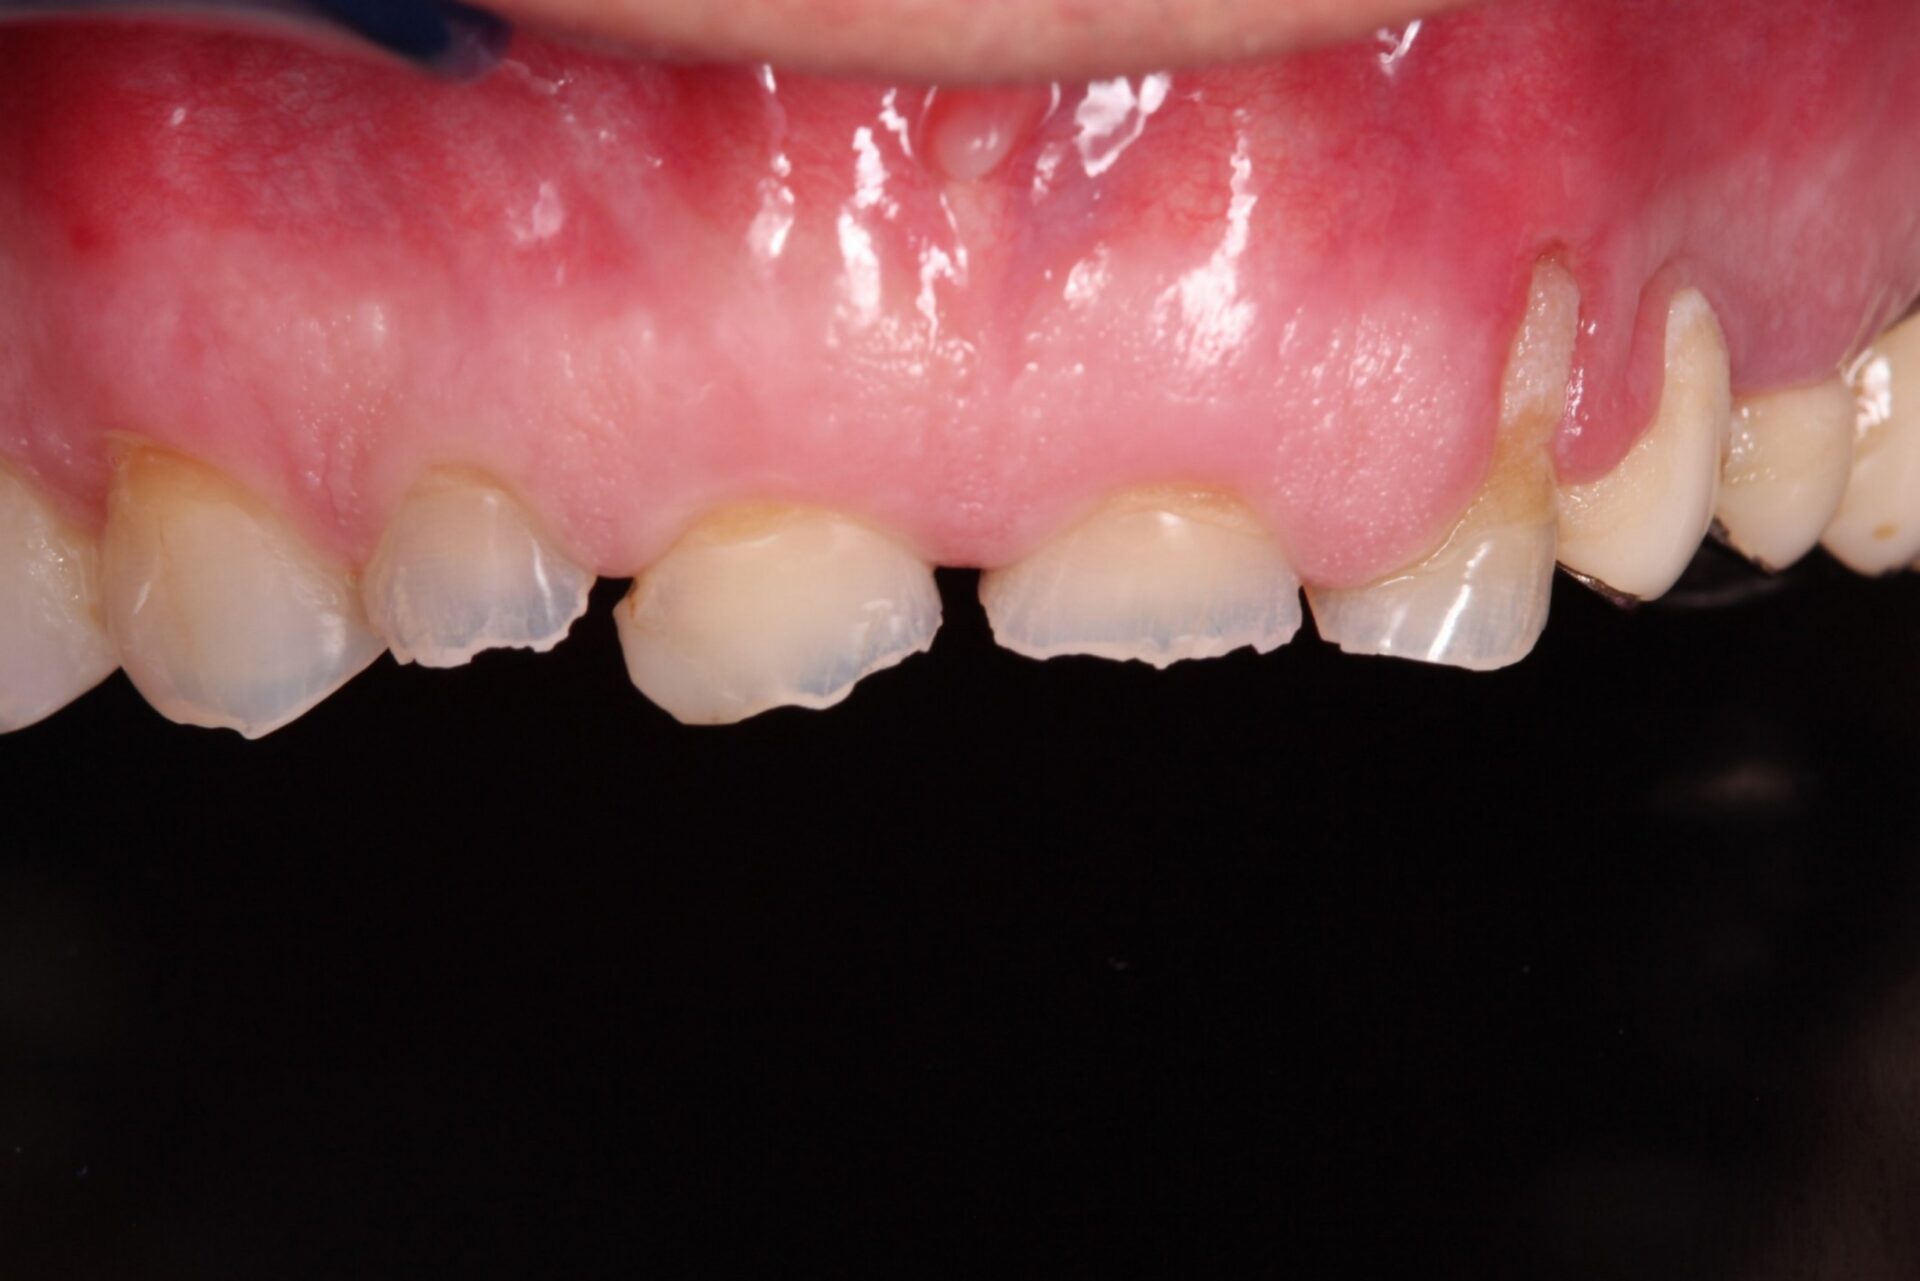

Ejemplo de un caso en paciente con erosiones:

- Antes – Inferior